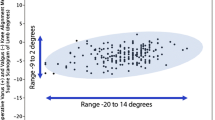

Kinematic alignment was performed with patient-specific instrumentation (PSI) in 995 knees (OtisMed Corporation, Alameda, CA, USA) until October 2009 and manual instruments were used in 2,217 knees with use of previously-described techniques [7, 11]. Both surgical techniques had the goal of setting the femoral component tangent to the distal and posterior native joint lines of the knee. The patient-specific instrumentation technique used a custom femoral cutting guide [12, 16]. The manual instrument technique used a distal offset cutting block to set the flexion-extension, varus-valgus, and proximal-distal positions of the femoral component [11]. Restoration of the distal and posterior native joint lines of the femur was achieved by adjusting the calipered measured thickness of the distal and posterior femoral resections until they equaled the thickness of the distal and posterior medial and lateral femoral condyles of the femoral component within ±0.5 mm after compensating for cartilage wear and kerf [11, 17, 18]. Both surgical techniques set the internal-external rotation of the A-P axis of the tibial component parallel to the flexion-extension plane of the extended knee and set the tibial component tangent to the varus-valgus plane and slope (i.e. flexion-extension) of the native proximal tibial joint line (Fig. 2) [11, 18]. Kinematic alignment with manual instruments set the slope of the tibial component by adjusting the inclination of an angel wing placed in the saw slot until parallel to the slope of the medial joint line [10, 11]. The varus-valgus plane of the tibial cut was fine-tuned without release of soft tissues until the varus-valgus laxity with trial components was negligible in full extension as in the native knee [11, 19]. All components were cemented. A post-operative X-ray of the operated knee was done in the recovery room, and on the day of discharge an anteroposterior, rotationally controlled, long-leg CT scanogram of the limb was obtained. Beginning in January 2010, axial CT scans of the knee were obtained with use of a previously described technique and were available for six of eight patients with tibial component failure and 18 of 24 patients in the matched control cohort [17, 18, 20].

The post-operative radiographic measurements and clinical characteristics were analyzed to determine differences between the TKAs with and without tibial component failure. Seven post-operative radiographic measurements were compared including flexion-extension of the femoral component, varus-valgus angle of the femoral component to the mechanical and anatomic axis of the femur, hip-knee-ankle angle of the limb, varus-valgus angle of the tibial component to the mechanical axis of the tibia, slope of the tibial component to the anatomic axis of the tibia, and internal-external rotation of the tibial component on the femoral component using previously described techniques (Fig. 3) [13, 16,17,18, 21]. One author (AJN) blinded to the patient group measured each radiographic measurement using previously described and validated techniques with use of image-analysis software (OsiriX Imaging Software, http://www.osirix-viewer.com) [20] (Fig. 3). Eight pre-operative clinical characteristics were compared including age, sex, body mass index (kg/m2), range of motion, varus-valgus deformity, and function scores (Table 3).

Nedopil AJ, Howell SM, Rudert M, Roth J, Hull ML (2013) How frequent is rotational mismatch within 0 degrees ±10 degrees in kinematically aligned total knee arthroplasty? Orthopedics 36(12):e1515–e1520

Nedopil AJ, Howell SM, Hull ML (2016) Does malrotation of the tibial and femoral components compromise function in kinematically aligned total knee arthroplasty? Orthop Clin North Am 47(1):41–50. doi:10.1016/j.ocl.2015.08.006